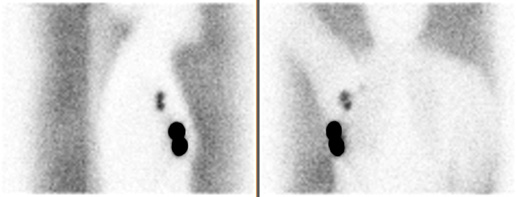

The usefulness at the acquisition in lateral projection in scintigraphic detection of sentinel lymph node in SNOLL examination in patients with breast cancer Streszczenie Wstęp: Rak piersi jest jednym z najczęściej występujących nowotworów u kobiet. Stanowi 20% wszystkich zachorowań na nowotwory, a w ostatnich kilku latach zachorowalność wzrosła o 4-5%. Dane przedstawione w Krajowym Rejestrze Nowotworów Złośliwych…